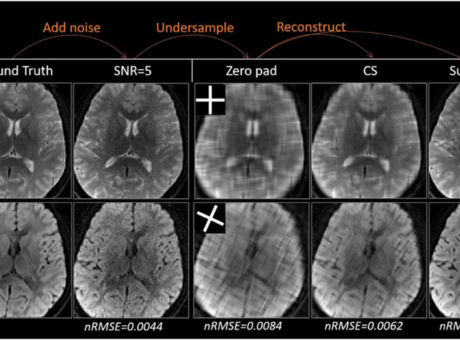

The lab highlights the growing impact of computational methods, combined imaging techniques, and animal models in advancing neuroscience research.